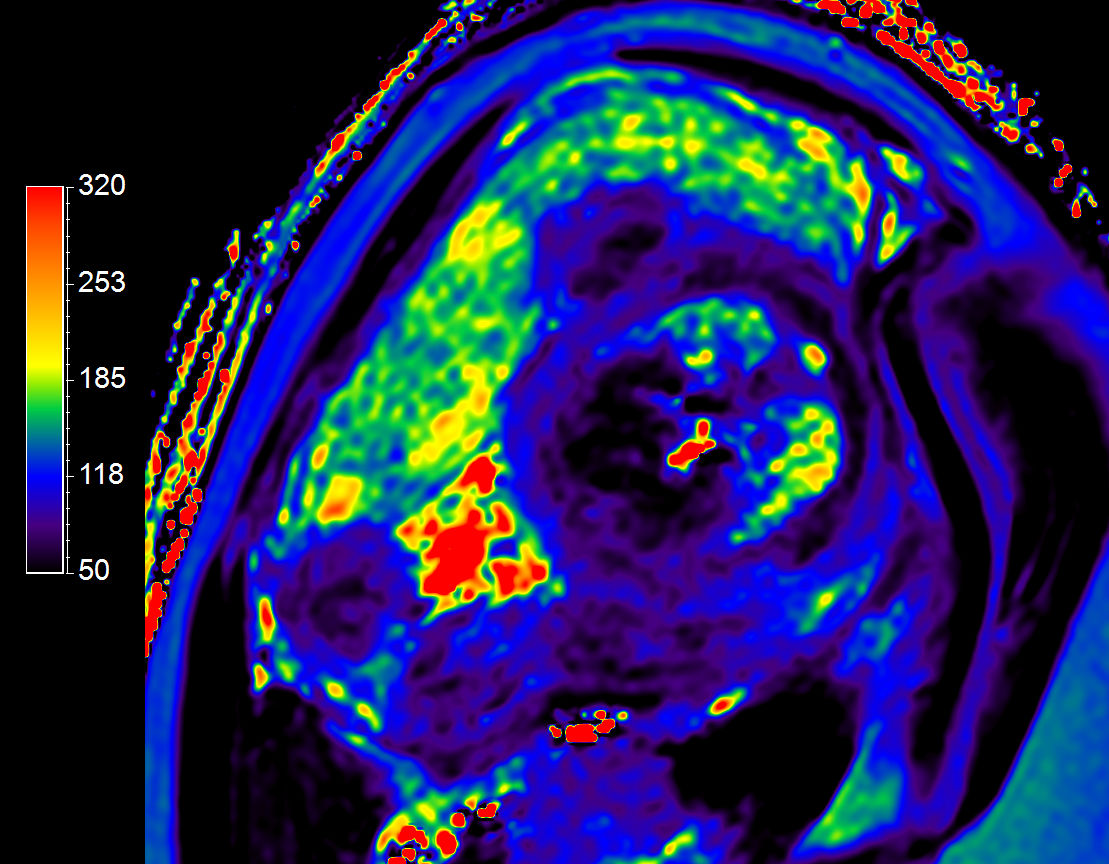

T2 Map

T2* Map